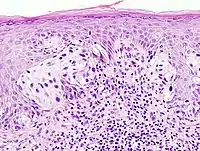

Many pathologists seek fellowship-level training, or otherwise pursue expertise in a focused area of surgical pathology. Subspecialization is particularly prevalent in the academic setting, where pathologists may specialise in an area of diagnostic surgical pathology that is relevant to their research, but is becoming increasingly prevalent in private practice as well. Subspecialization has a number of benefits, such as allowing for increased experience and skill at interpreting challenging cases, as well as development of a closer working relationship between the pathologist and clinicians within a subspecialty area. Commonly recognized subspecialties of surgical pathology include the following:

- Dermatopathology (A board-certifiable subspecialty in the U.S.)